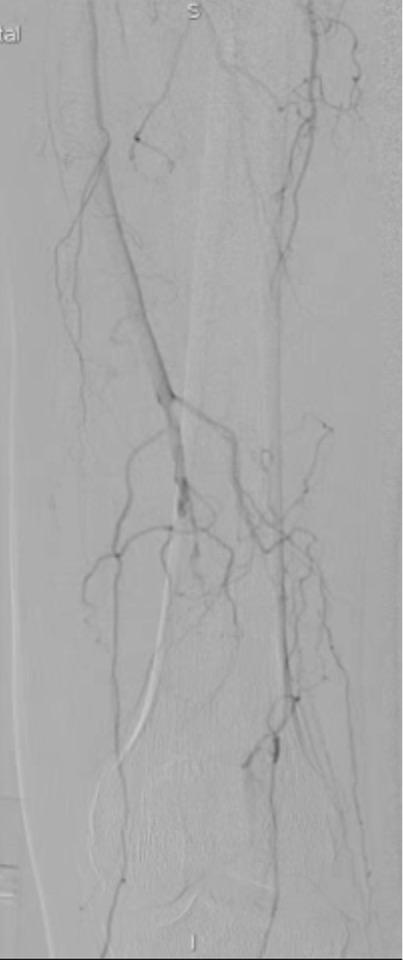

最后的结果令人满意,而且达到了患者的诉求,尽量不植入支架,来看看最后的造影结果吧